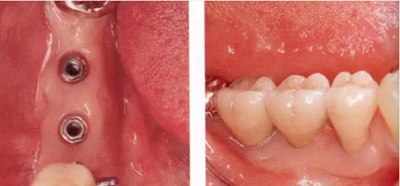

▲圖10-3,4

圖10-3 第二次手術前的(牙合)面照。

圖10-4 為了在頰側、舌側進行FGG,在上頜腭側采集大塊移植片

▲圖10-5,6

圖10-5 第二次手術后的舌側面照。遠中側進行APF,近中側進行FGG。

圖10-6 頰側也進行FGG,縫合后確認移植片不會移動。